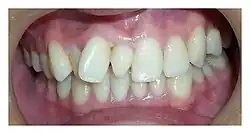

| Intraoral photograph showing conical mesiodens | |

The most common supernumerary tooth is a mesiodens, which is a malformed, peg-like tooth that occurs between the maxillary central incisors.